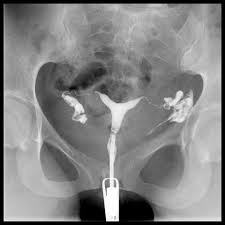

Şekle bakıldığında rahim filmi çekilirken rahim ağzından verilen maddenin hem rahim içinden hemde tüplerden geçtiği görülebilir.

Film çekildiğinde yukarıdakine benzer bir görüntü elde edilir.